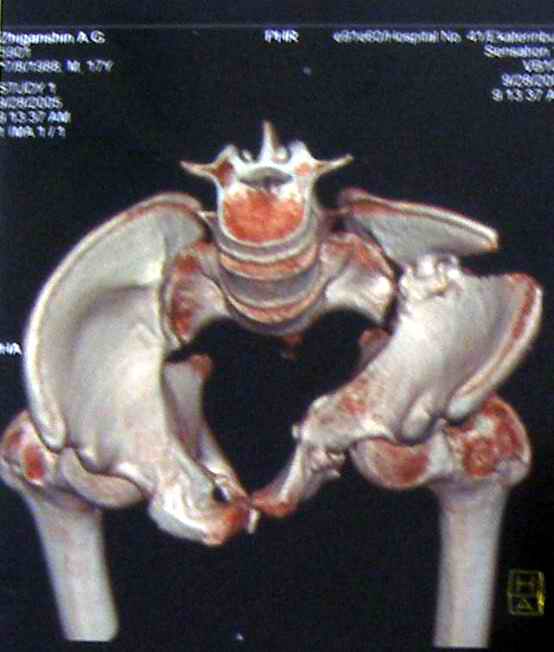

Коллеги, помогите определиться с тактикой лечения пациента. Ув. коллеги, к нам поступил молодой человек 17 лет. Травма в июле 2005- ДТП, т.е. 3 мес назад. Лечился консервативно в "гамаке" 1,5 мес., затем ходьба с костылями без опоры на левую нижнюю конечность, начал на нее опираться 1 нед назад. В настоящее время имеется укорочение порядка 4-5 см, выраженная хромота, передвигается с одним костылем. Кроме того беспокоят боли в пояснично-крестцовой области при ходьбе, неудобство при сидении, невозможность лежать на спине "на жестком", а также на левом боку (субъект худощавый, боль в области крыла) хромота, длительное пребывание на ногах невозможно. На функциональных снимках большой подвижности нет (не привожу из-за плохого качества). Учитывя наличие участков сращений, помогите опредилиться с тактикой. Наш план пока такой: 1. выполнить остеотомии в участках сращений 2.постепенно аппаратом низвести смещенную половину таза. 3.выполнить внутренний остеосинтез передних и задних отделов. Будем признательны за ваш взгляд на тактику леченияэтого больного, а так же на такие проблемы как: места остеотомий, возможные варианты компоновки аппарата, выбор имплантатов для последующего вмешательства.